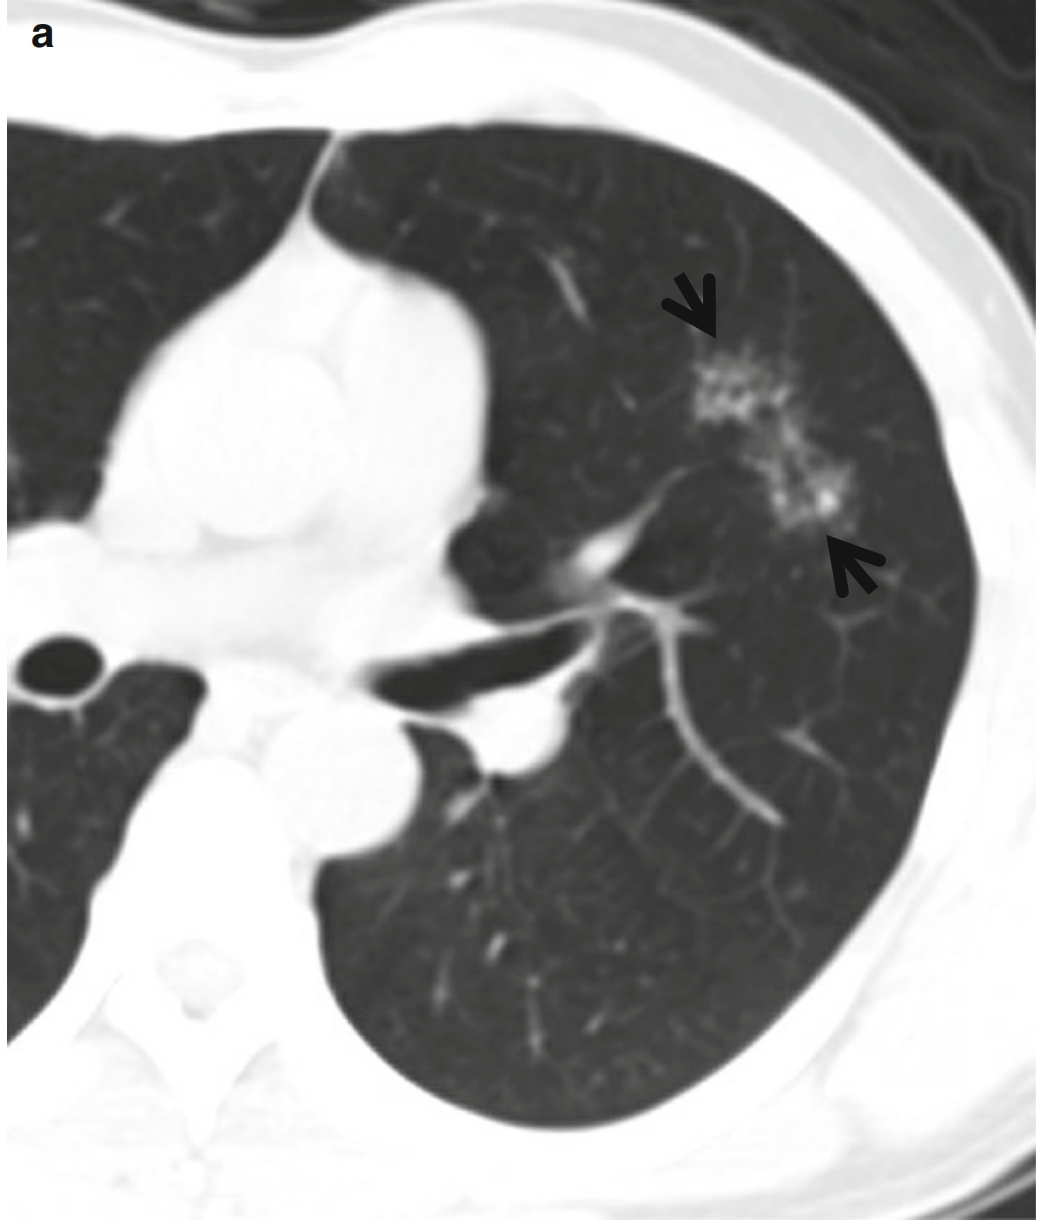

由多个小结节组成的一个大结节,其周围存在许多小得多的卫星结节,称作星系征(图1)。

图1,CT星系征。男,23岁、肺结节病患者。连续薄层CT扫描(层厚=2.5mm)于右肺上叶支气管水平可见多发星系征(箭头所示),由多个小结节和周围多发非常小的卫星病灶组成、以右肺上叶最为明显。纵隔窗(此处未给出)可见纵隔和双侧肺门增大的淋巴结影。